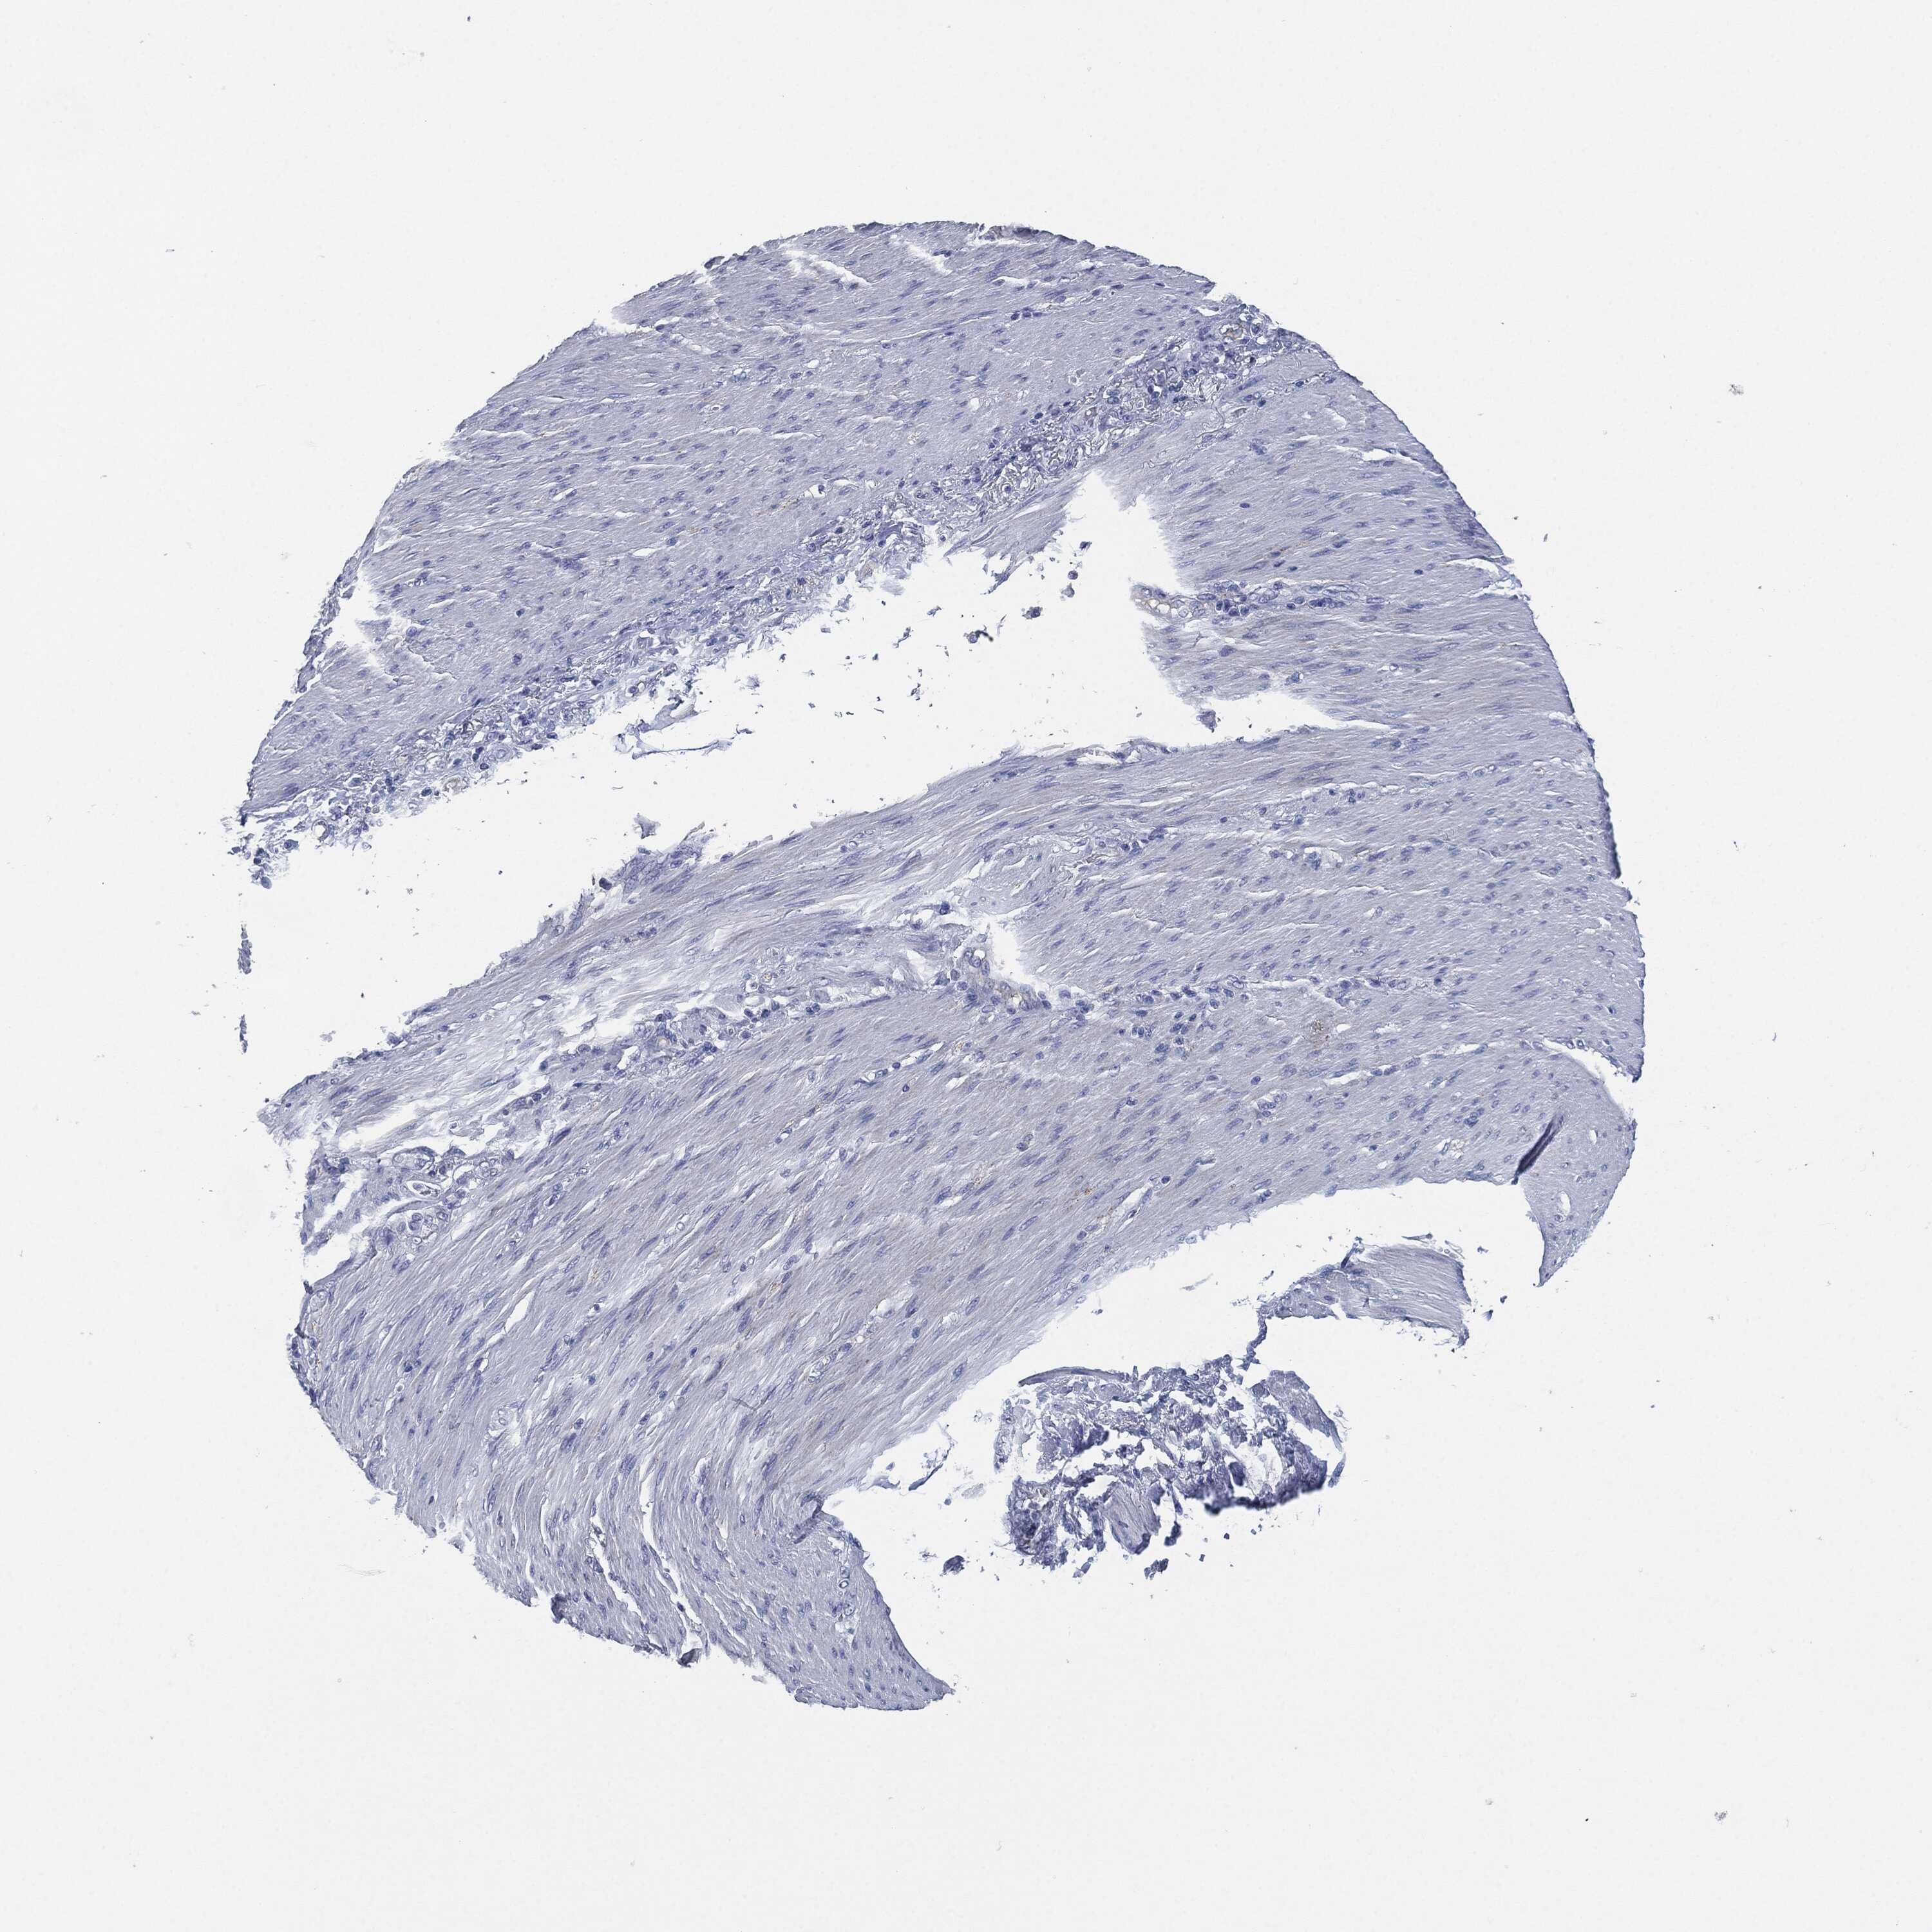

STOMACH CANCER - Protein expressioni

A mouse-over function shows sample information and annotation data. Click on an image to view it in a full screen mode. Samples can be filtered based on level of antibody staining by selecting one or several of the following categories: high, medium, low and not detected. The assay and annotation is described here.

Note that samples used for immunohistochemistry by the Human Protein Atlas do not correspond to samples in the TCGA dataset.

Antibody stainingi

Antibody staining in the annotated cell types in the current human tissue is reported as not detected, low, medium, or high, based on conventional immunohistochemistry profiling in selected tissues. This score is based on the combination of the staining intensity and fraction of stained cells.

Each image is clickable and will lead to virtual microscopy that enables deeper exploration of all samples and also displays staining intensity scores, fraction scores and subcellular localization as well as patient and tissue information for each sample.

Antibody HPA038936

Antibody CAB002420

Antibody CAB080304

Staining

High

Medium

Low

Not detected

Intensity

Strong

Moderate

Weak

Negative

Quantity

>75%

75%-25%

<25%

None

Location

Nuclear

Cytoplasmic/membranous

Cytoplasmic/membranous,nuclear

Adenocarcinoma, NOS

Adenocarcinoma, High grade